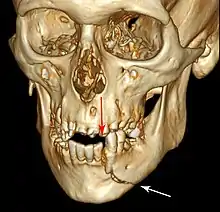

| 3D computed tomographic image of a mandible fracture in two places. One is a displaced right angle fracture and the other is a left parasymphyseal fracture. | |

Computed tomography is the most sensitive and specific of the imaging techniques. The facial bones can be visualized as slices through the skeletal in either the axial, coronal or sagittal planes. Images can be reconstructed into a 3-dimensional view, to give a better sense of the displacement of various fragments. 3D reconstruction, however, can mask smaller fractures owing to volume averaging, scatter artifact and surrounding structures simply blocking the view of underlying areas.

3D CT reconstruction of mandible fracture, white arrow marks fracture, red arrow marks moderate displacement and open bite